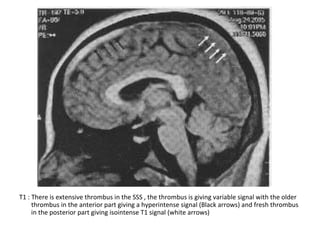

T1 : There is extensive thrombus in the SSS , the thrombus is giving variable signal with the older

thrombus in the anterior part giving a hyperintense signal (Black arrows) and fresh thrombus

in the posterior part giving isointense T1 signal (white arrows)